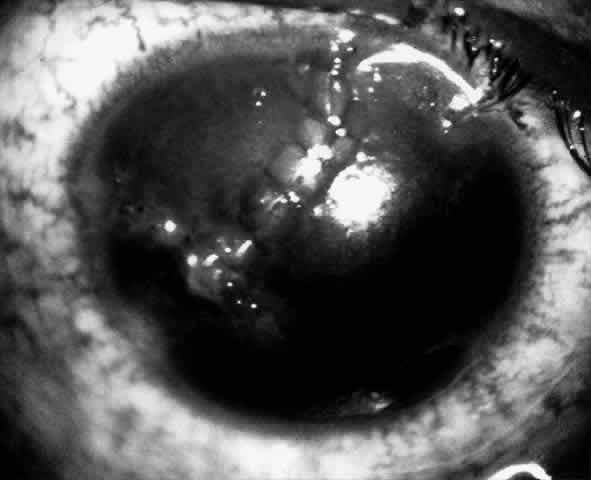

Bowman's layer in the tissue lens seems to undergo some deterioration if the surface is not covered by epithelium within 7 to 10 days.14 Therefore, if an epithelial defect persists beyond this period (Fig. 15), it is worth considering removing the lenticule and replacing it with a different lenticule when the eye is no longer irritated.

Fig. 15. A persistent epithelial defect in a lenticule being removed because of failure to epithelialize.